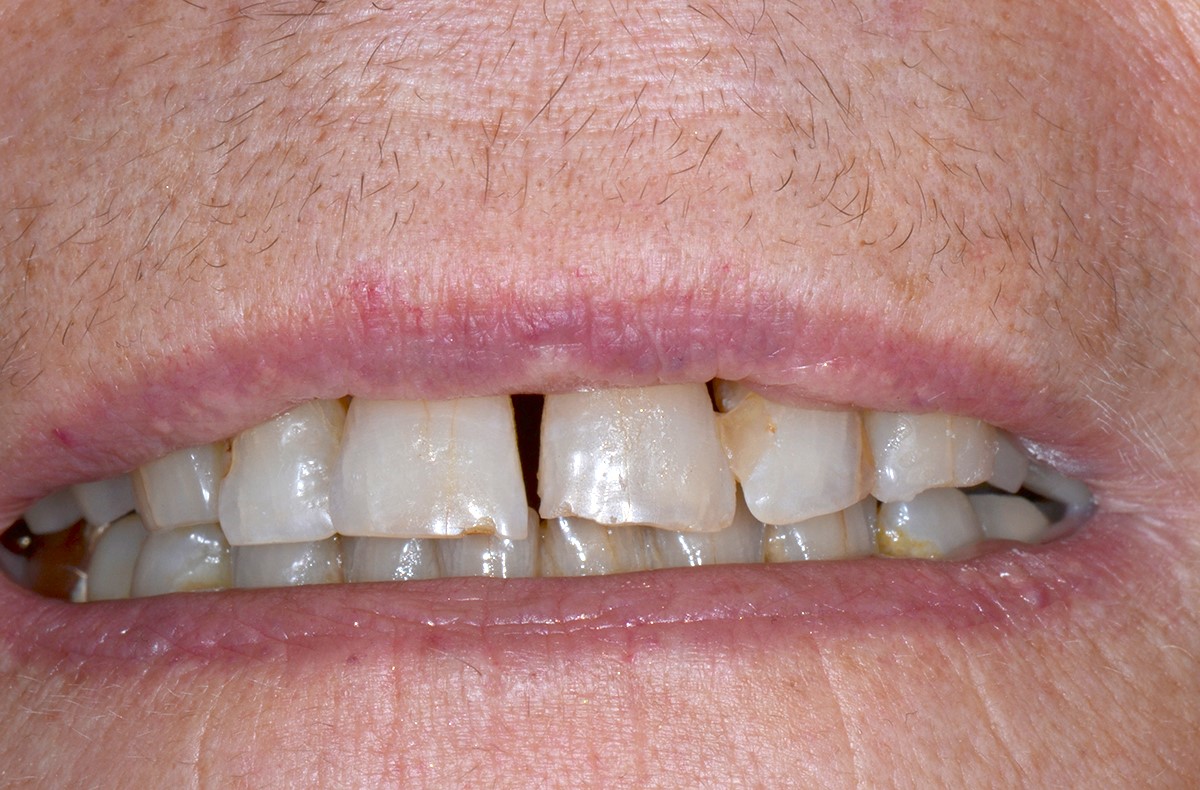

Chute de la patiente ayant entrainé des fractures des incisives.

Des couronnes tout en céramique sont réalisées afin de redonner le sourire à la patiente.